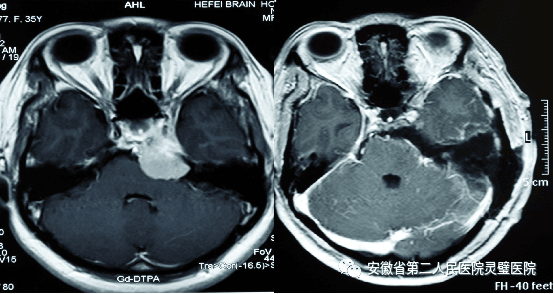

二、神经肿瘤的综合治疗技术

常规开展各型颅内及脊髓肿瘤手术,包括鞍区肿瘤、斜坡肿瘤、后颅窝等颅底肿瘤,尤其在听神经瘤、颅咽管瘤、垂体瘤等治疗方面处于国内领先水平。系统开展胶质瘤的综合治疗,并结合肿瘤基因指标,提升胶质瘤的放化疗效果,极大提高5年的存活率。

垂体瘤手术前后

岩斜区脑膜瘤术前及术后